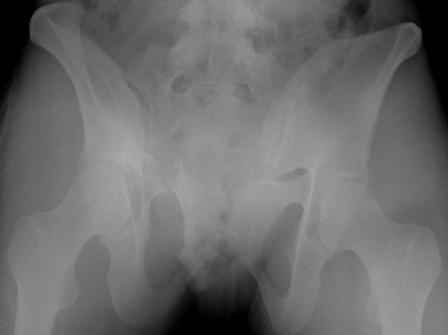

Re: перелом таза

Серия до- и послеоперационных снимков этой пациентки. Хотя бы post factum обсудить. Не знаю, что можно сделать с задними отделами стержневым аппаратом, но три крепких парня открытым путем с помощью "волшебных" слов еле-еле смогли отрепонировать - сзади все было очень ригидно!